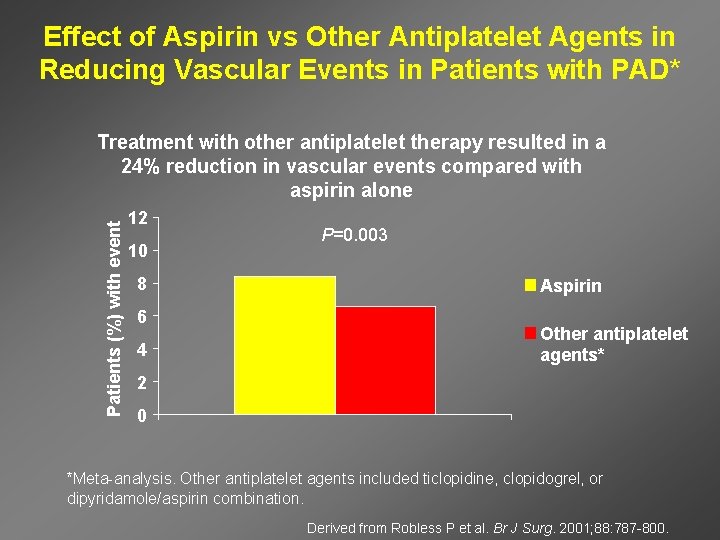

Effect of Aspirin vs Other Antiplatelet Agents in Reducing Vascular Events in Patients with PAD* Patients (%) with event Treatment with other antiplatelet therapy resulted in a 24% reduction in vascular events compared with aspirin alone 12 10 8 6 4 P=0. 003 Aspirin Other antiplatelet agents* 2 0 *Meta-analysis. Other antiplatelet agents included ticlopidine, clopidogrel, or dipyridamole/aspirin combination. Derived from Robless P et al. Br J Surg. 2001; 88: 787 -800.